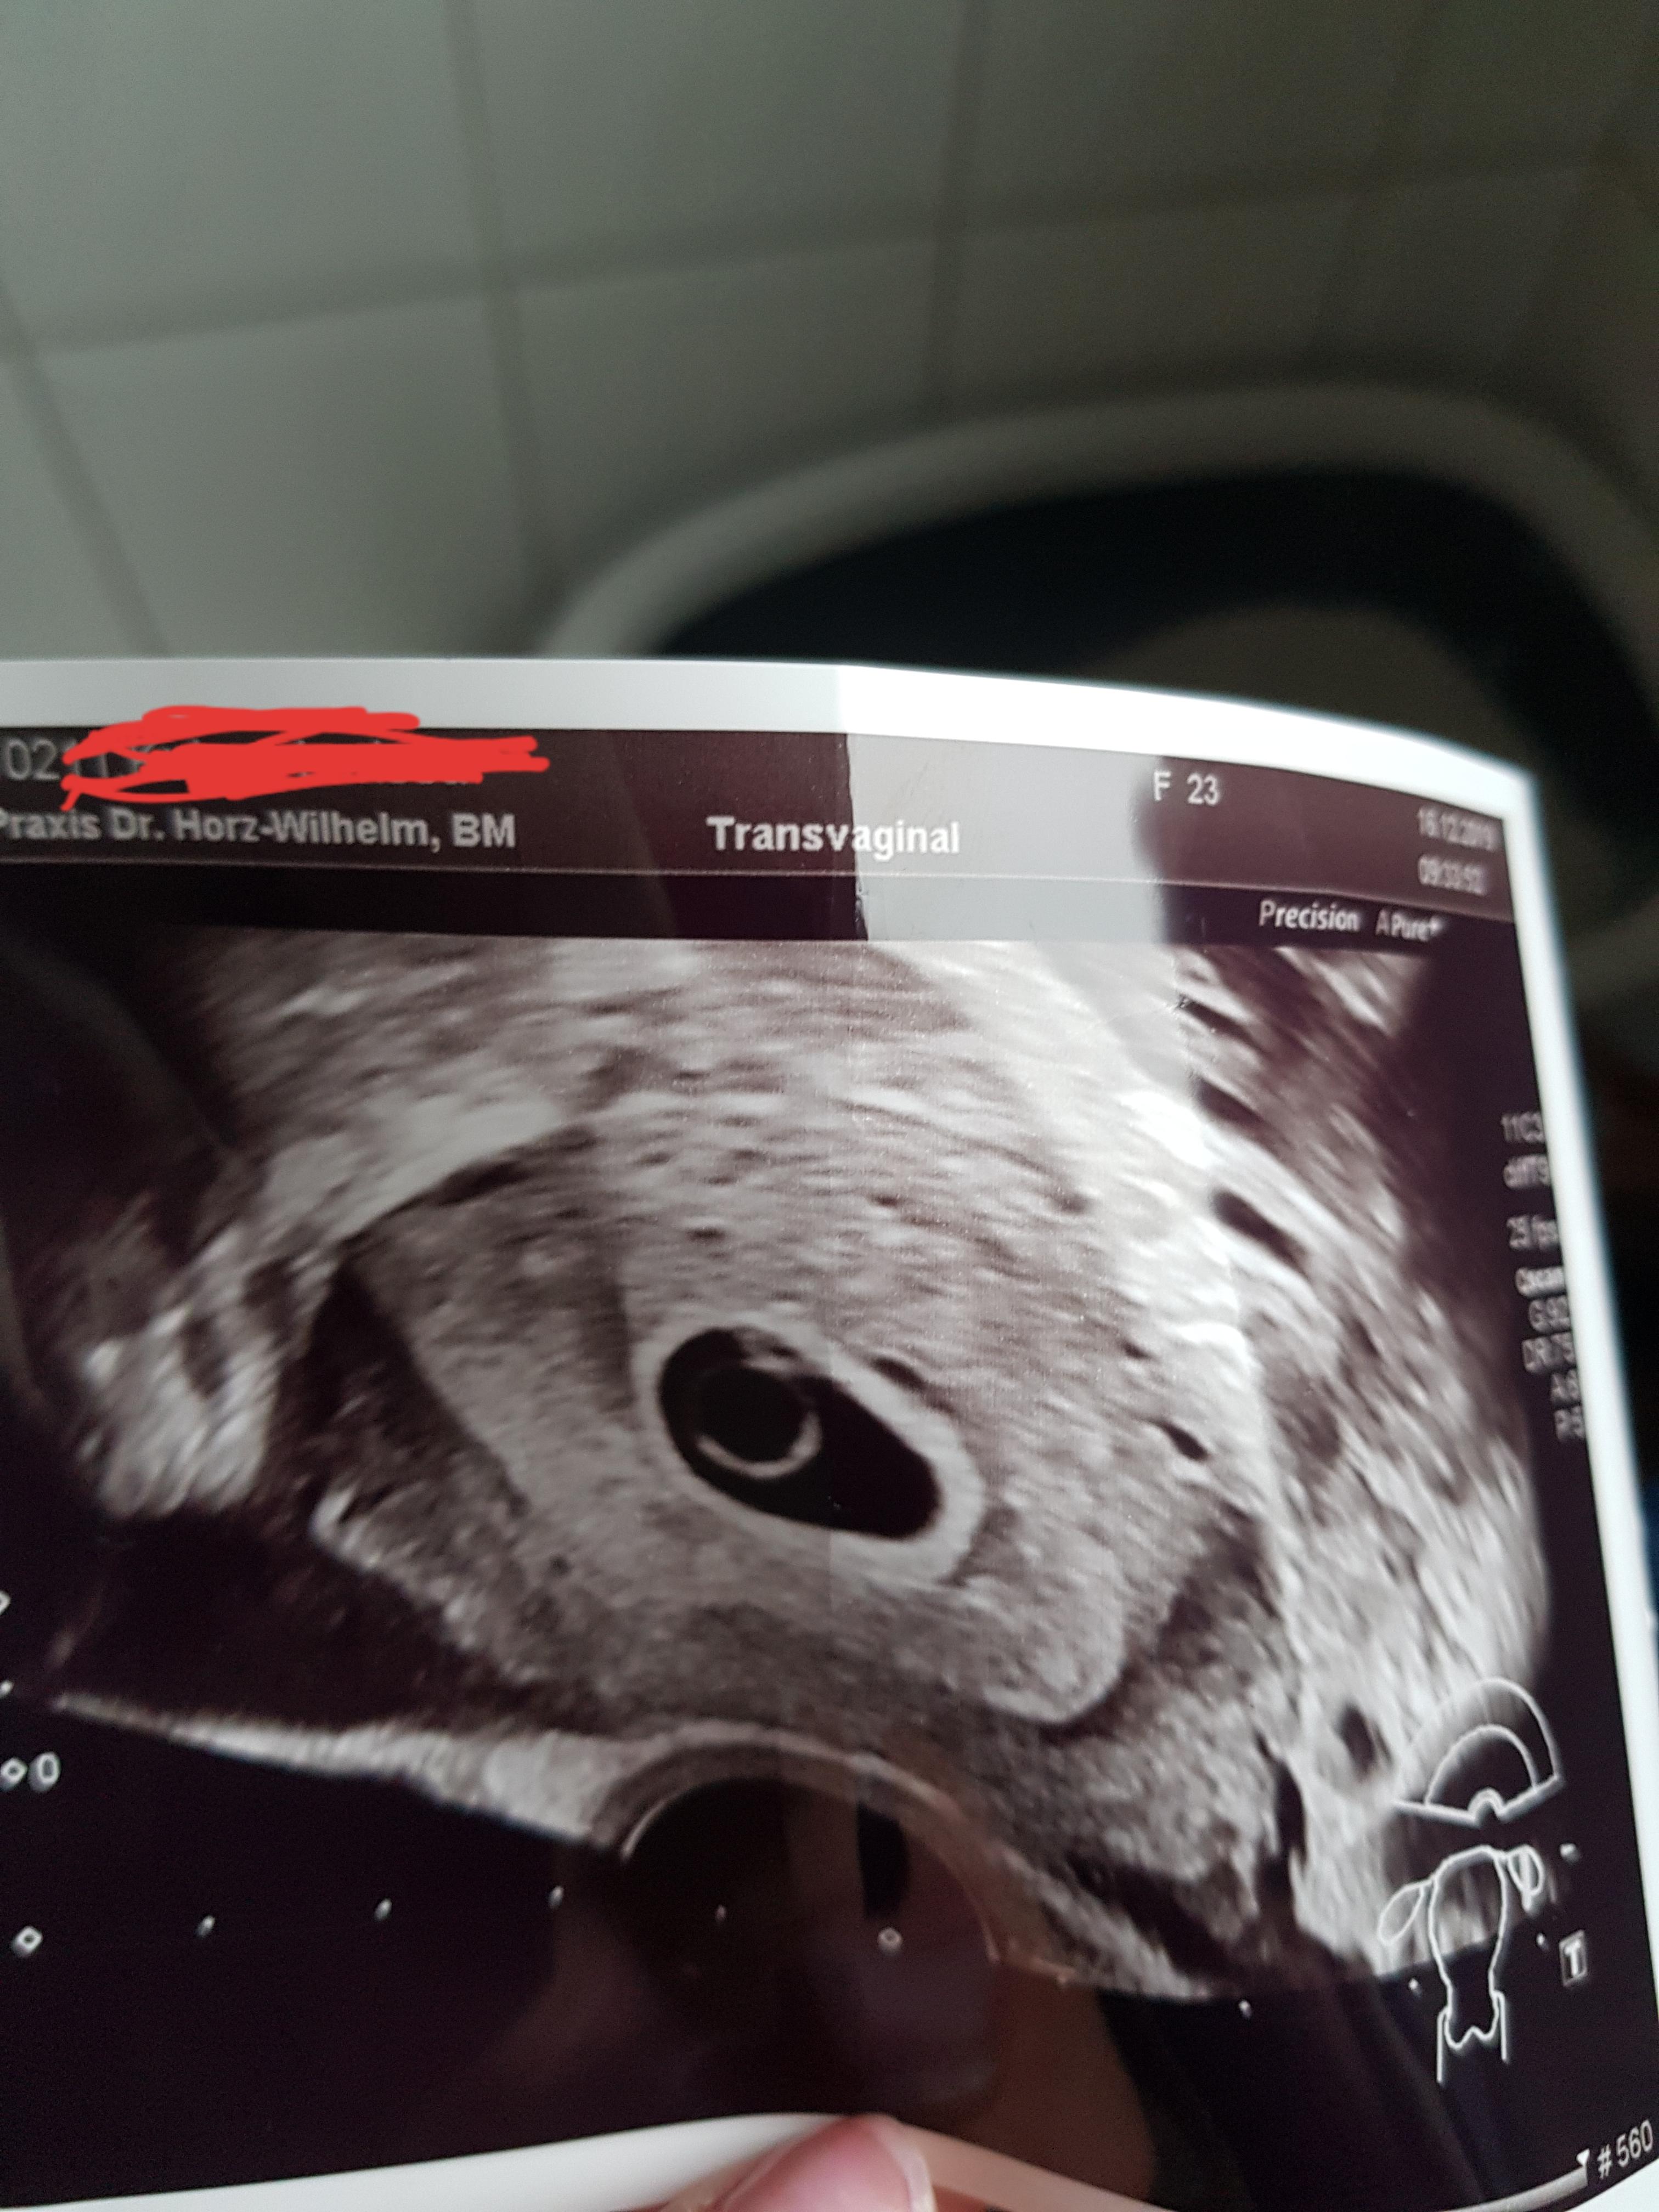

8 SSW Ultraschall Deines Babys in der 8 Schwangerschaftswoche In der 8 SSW ist der Embryo 16 Millimeter groß Ab Ende dieser Woche ist sogar der Herzschlag beim Ultraschall zu erkennen und Herz und Kopf sind getrennt voneinander darstellbar In der jetzigen Entwicklungsphase tritt eine kleine Schleife des Darmes in einen Abschnitt der Nabelschnur über, weil die Bauchhöhle noch zu klein. Zwar kann der Herzschlag des Embryos bereits gegen Ende der 6 Schwangerschaftswoche zu erkennen sein, doch auch wenn euer Frauenarzt das Herz auf dem Ultraschall noch nicht pochen sieht, braucht ihr euch keine Sorgen zu machen Spätestens in der 8 Schwangerschaftswoche ist der Herzschlag erkennbar Ob der Herzschlag bereits in der 6. Zwar kann der Herzschlag des Embryos bereits gegen Ende der 6 Schwangerschaftswoche zu erkennen sein, doch auch wenn euer Frauenarzt das Herz auf dem Ultraschall noch nicht pochen sieht, braucht ihr euch keine Sorgen zu machen Spätestens in der 8 Schwangerschaftswoche ist der Herzschlag erkennbar Ob der Herzschlag bereits in der 6.

Hallo, ich brauche mal ein paar Infos und Erfahrungen von euchHier die "Fakten" nach Eisprung gerechnet bin ich schwanger bei 73 Schwangerschaft wurde Anfang 6 Woche vom Arzt bestätigt, soweit alles iO, nur noch kein Herzschlag außerdem. Größe und Entwicklung des Embryos in der 7 SSW In der 7 Schwangerschaftswoche (60 bis 66) wird Ihr Baby fünf Wochen alt und 5 mm groß Das Herz schlägt ungefähr 150 Mal in der Minute Ihr Kind bekommt langsam ein Gesicht Noch seitlich am Kopf sind die Augen deutlich erkennbar bisher ohne Lider. 8 SSW Ultraschall Deines Babys in der 8 Schwangerschaftswoche In der 8 SSW ist der Embryo 16 Millimeter groß Ab Ende dieser Woche ist sogar der Herzschlag beim Ultraschall zu erkennen und Herz und Kopf sind getrennt voneinander darstellbar In der jetzigen Entwicklungsphase tritt eine kleine Schleife des Darmes in einen Abschnitt der Nabelschnur über, weil die Bauchhöhle noch zu klein.

Der Herzschlag ist zwar noch relativ unauffällig, aber dennoch zu sehen Was demnach 7 SSW 0, 1, 2 oder 3 bedeutet, hat dir dein Gynäkologe bestimmt erklärt Steht in deinem Mutterpass also etwa 7 SSW 4 oder 5, dann bist du bereits in der 8 Schwangerschaftswoche (SSW) Auch der errechnete Geburtstermin kann in den Mutterpass. Dein Körper in der 7 SSW Der ab der 7 SSW sichtbare Herzschlag Deines Babys wird sicherlich auch Dein Herz höher schlagen lassen Glücksmomente wie diese schütten ein Wohlfühlhormon aus, dass Deine Stimmung steigen lässt Genieß den Moment, der Dich Beschwerden und Zukunftssorgen vergessen lässt. 7 SSW Entwicklung des Babys Von außen sind noch keine Anzeichen zu erkennen (Sebastian Kaulitzki / Fotoliacom) In der 7 Schwangerschaftswoche ist der Embryo 5–8 mm groß und wiegt in etwa ein Gramm Die Fruchthöhle ist mit einer Größe von 25 mm schon eindeutig zu sehen Der Kopf wächst in diesen en besonders schnell.